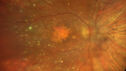

79 year old vision is in for a checkup with no visual complaints in the left eye. This is her better eye. VA 20/200 OD, 20/50 OS. 3 years ago she had a CRVO in the left eye. She is also diabetic for 20 years, has carotid insufficiency and anemia. Left eye shows CME. This was not treated and the vision improved to 20/40 over the next year although mild edema persisted.